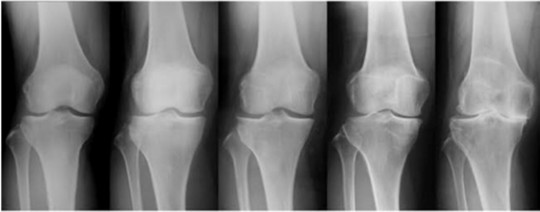

正常な膝

痛みが出た膝

痛みが繰り返される膝

初期 変形性膝関節症

末期 変形性膝関節症

へと移行する流れになっている。

初期 変形性膝関節症で食い止める必要がある。

でなければ、手術になる可能性が高くなっていく。